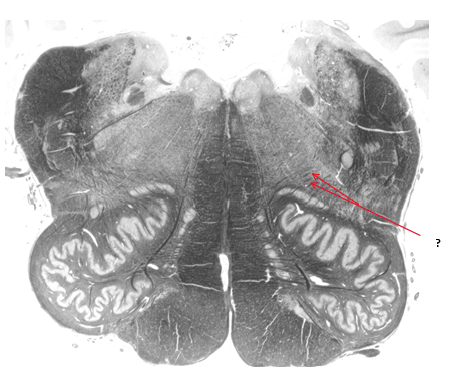

Name this and state its function within its 2 parts.

Olive.

Inferior: integrates motor and sensory function

Superior: sound localisation.